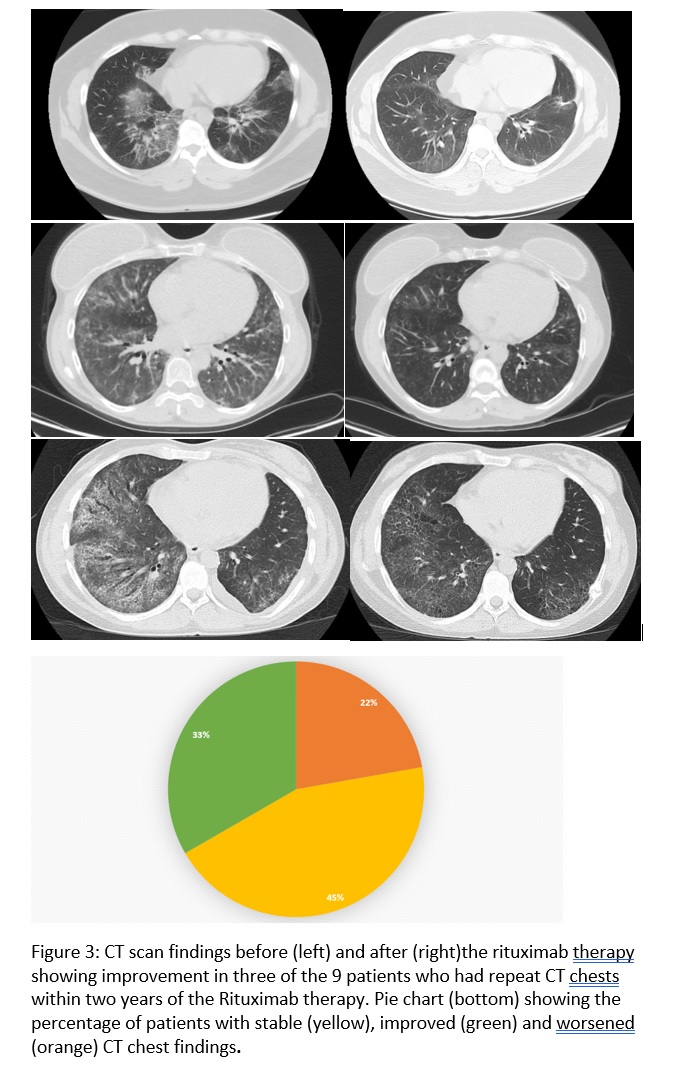

Results: Of the 791 patients in the registry, 14 patients met the criteria for IPAF and received at least one dose of Rituximab. 19 patients were identified who met the criteria for IPAF and did not receive Rituximab to serve as the control group. There were no differences in the baseline demographics. Five patients (45.4%) in the RTX group were improved and 4 (36.3%) remained with stable FVC and DLCO. Accordingly, HRCT scan findings improved in 3 (33%) patients and remained stable in 4 (45%), from 9 patients with available HRCT scans. Frequency of oxygen use, incidence of infection, respiratory related admissions and overall mortality was similar in both the groups.